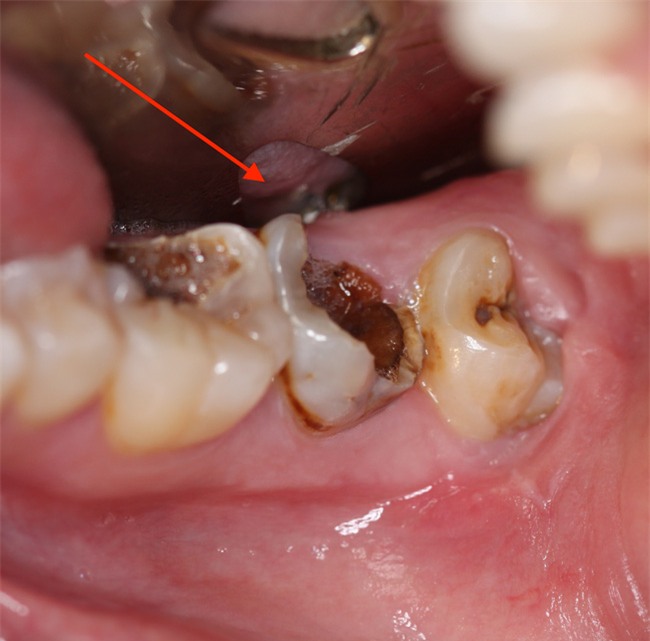

Trong các bệnh về răng miệng, sâu răng là một trong những căn bệnh cực phổ biến ở mọi độ tuổi. Không chỉ có trẻ em, người lớn, người cao tuổi cũng thường bị sâu răng. Nguyên nhân bắt nguồn từ việc chúng ta ít quan tâm đến chăm sóc sức khỏe răng miệng.